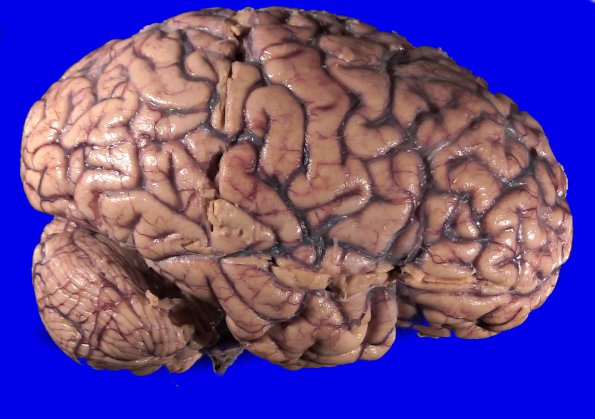

A right lateral hemispheric view shows atrophy of frontal, temporal and parietal lobes.